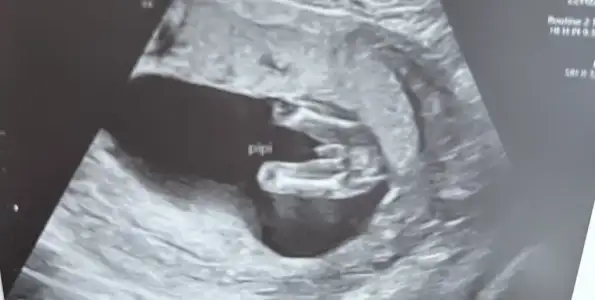

Kac haftalikken bu fotograf acaba

Aaaa hayırlı olsun kızınızkediannesibiri ya kızlar ben detaylıdan çıktım her şey süper yüzü de bir güzel görseniz ama tek bir sorun var erkek değilmiş

Testler karışmış doktor bembeyaz oldu

Kızım oluyor kızııımmmm.

Ay çok tatlı bir süpriz olmuşşkediannesibiri ya kızlar ben detaylıdan çıktım her şey süper yüzü de bir güzel görseniz ama tek bir sorun var erkek değilmiş

Sonuç da kız ama doktor yorgunluktan yanlış okumuşAaaa hayırlı olsun kızınızfetal dna sonucuna göre mi erkek demişti